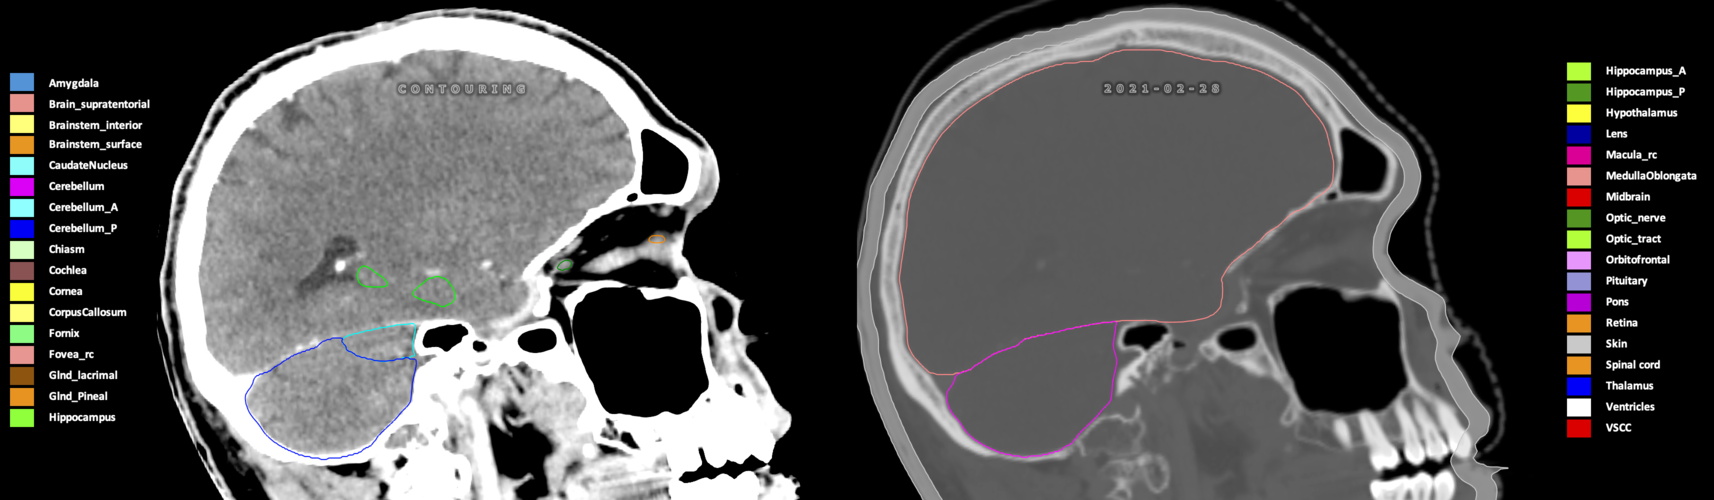

Included are all OARs known to be relevant for radiation-induced toxicity in neuro-oncology: brain, brainstem (midbrain, pons, medulla oblongata), chiasm, cerebellum (anterior & posterior), cochlea, cornea, hippocampus (anterior & posterior), hypothalamus, lens, lacrimal gland, optic nerve, pituitary, skin, and vestibular & semicircular canals. To further facilitate research on cognition, vision and radiological changes after irradiation of the brain, potential clinically-relevant OARs are included: amygdala, caudate nucleus, cerebellum (anterior & posterior), corpus callosum, fornix, macula, optic tract, orbitofrontal cortex, periventricular space (PVS), pineal gland, and thalamus.

Three-dimensional delineation of the 25 consensus OARs for neuro-oncology are shown on CT (WW/WL 120/40, 3000/600), 3T MR images, (T1Gd, T2FLAIR 1mm) and 7T MR (MP2RAGE 0.7 mm). All are presented in transversal, sagittal and coronal view.